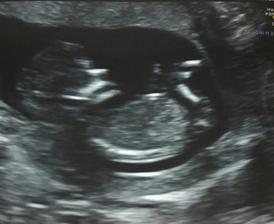

@sun89 Ahojky, trapi me otoky a vysoky tlak jak ten normalni tak i nitroocni, tak uvidime, jak budu/nebudu rodit. Jinak to bude chlapeček a jmeno vybrane už take mame❤😍❤ Jen jdu ted 26.9. znovu na ocni, co teda a jak😉 Manzel vcera prekvapil, ze chce jit k porodu, celou dobu nechtel a teď že ano🤔😎